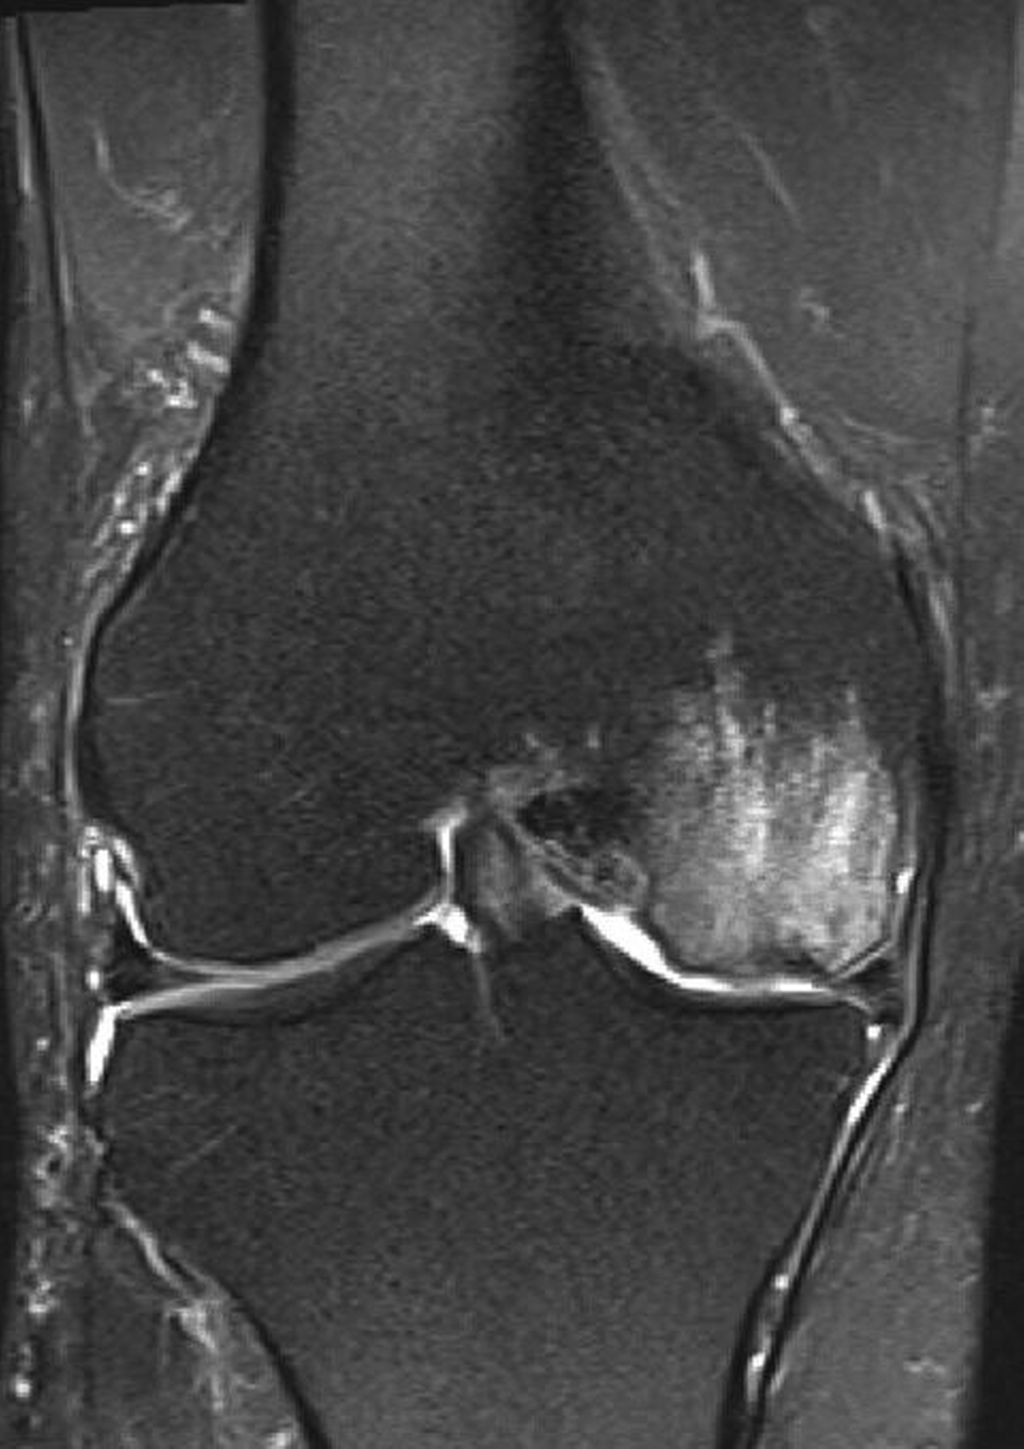

Abb. 3: Postoperatives Bild nach Implantation einer medialen Hemischlittenprothese

Ein 62-jähriger Patient stellte sich im März 2025 mit belastungsabhängigen Knieschmerzen rechts vor. Im MRT zeigte sich eine Läsion des medialen Meniskus, sodass in Zusammenschau mit dem positiven Meniskuszeichen in der klinischen Untersuchung eine partielle Meniskektomie durchgeführt wurde. Die postoperative Phase verlief zunächst unauffällig. Der Patient berichtete über ein beschwerdefreies Intervall von rund sieben Wochen. Anschließend entwickelten sich jedoch erneut zunehmende Schmerzen im rechten Kniegelenk, die eine erneute Vorstellung in der Spezialambulanz erforderlich machten. Er berichtete vor allem über belastungsabhängige Schmerzen im Bereich des medialen Kniegelenks. Daraufhin wurde ein Ganzbeinröntgen zur Beurteilung der Beinachse durchgeführt, hier zeigte sich eine varische Beinachse mit 5 Grad Varus (Abb.1). In der ergänzend durchgeführten MRT-Untersuchung konnte medialseitig eine ausgeprägte Nekrosezone am medialen Femurkondyl nachgewiesen werden (Abb.2). Schlussendlich wurde aufgrund dieses Befundes die Indikation zur Implantation einer medialen Hemischlittenprothese rechts gestellt, die schließlich im August 2025 komplikationslos durchgeführt wurde (Abb.3+4).